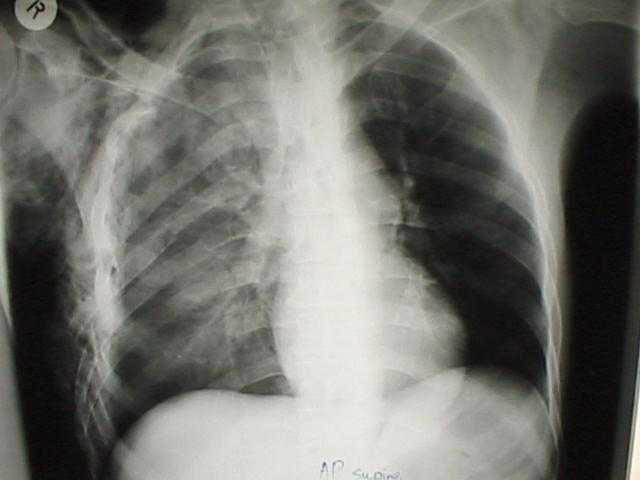

A patient with chest trauma. What radiographic abnormalities can be seen in this supine chest X ray?

A contusion of the left lung (diffuse consolidation with not clearly defined borders), rib fractures and subcutaneous emphysema (air in the subcutaneous tissue appearing as black areas)

Image from theWikipedia.org (Karim) https://en.wikipedia.org/wiki/Chest_injury#/media/File:Pulmonary_contusion.jpg